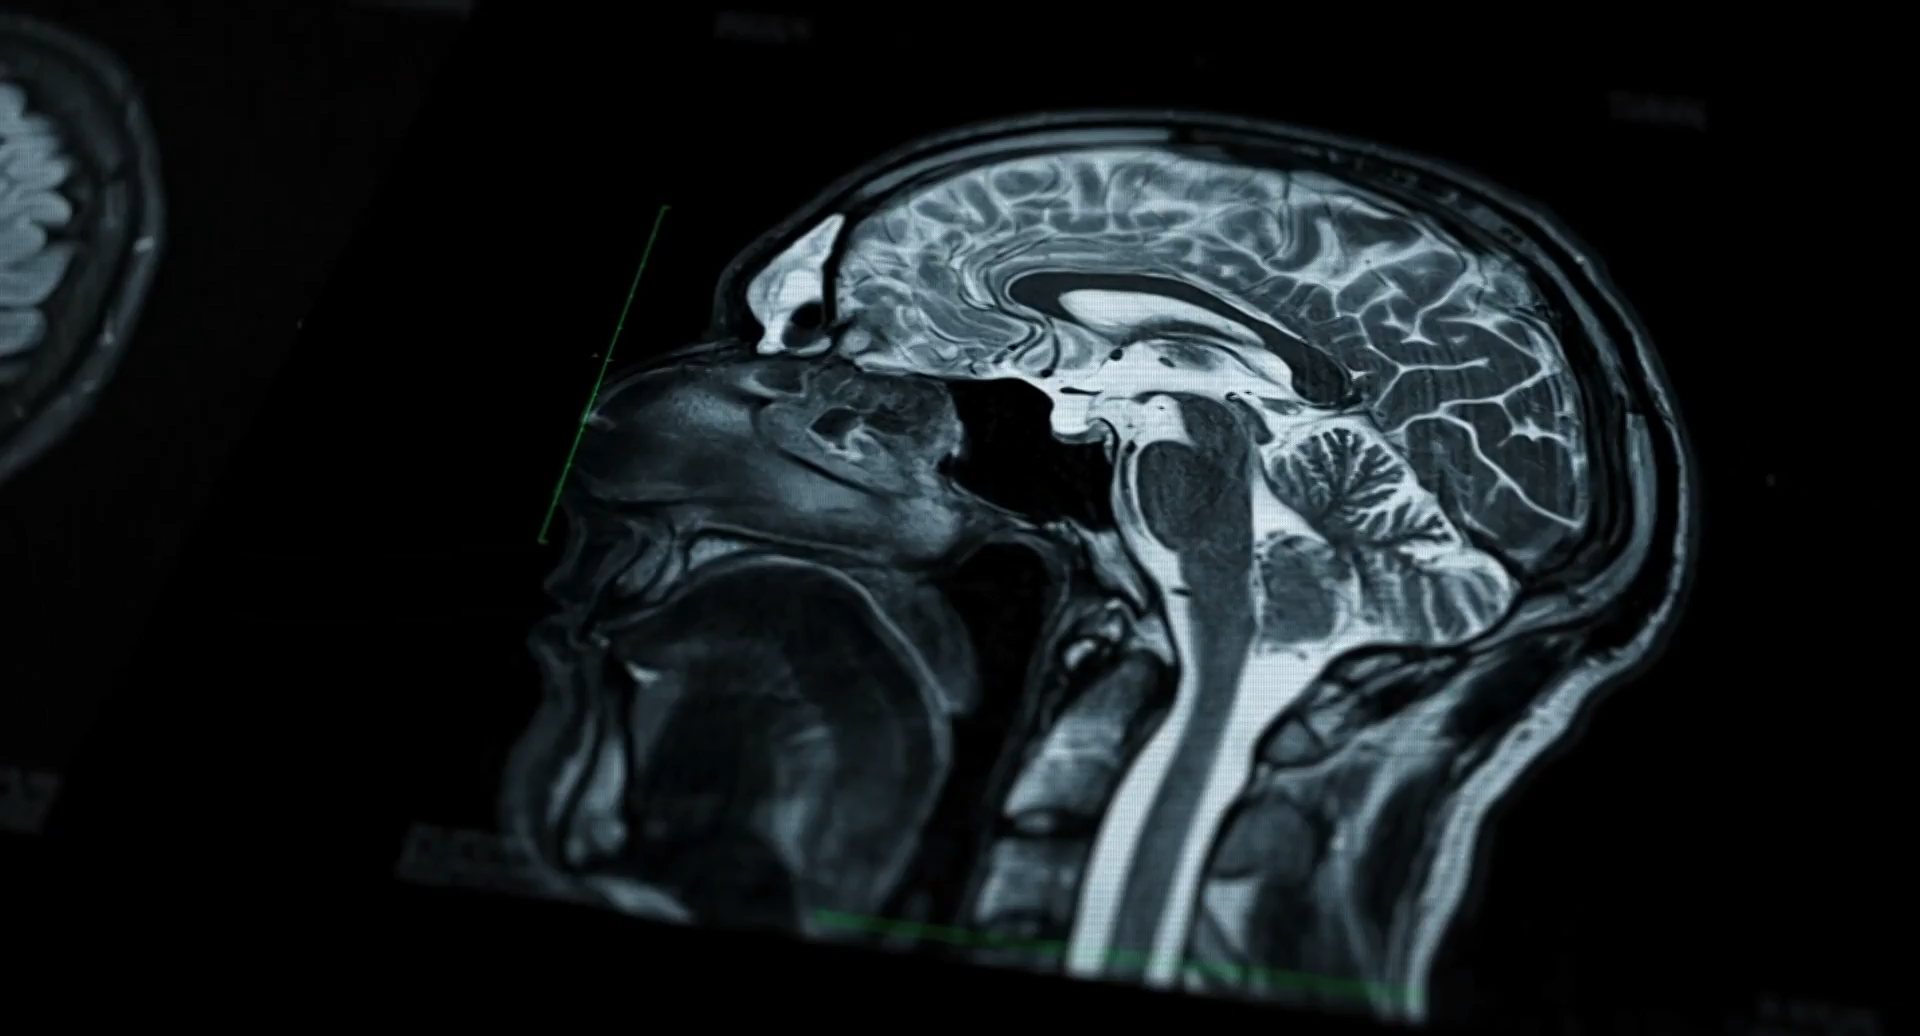

Zentrum für innovative Radiologie